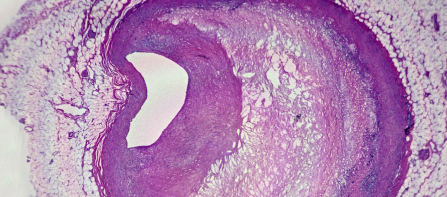

今年 3 月,意大利的一项小型研究发现,在接受动脉疏通手术的患者体内切除的脂肪沉积物中,发现了微塑料碎片,并在近 3 年后报告了他们的健康状况。

通过颈动脉内膜切除术去除狭窄动脉中的脂肪斑块可以降低未来中风的风险。

研究人员对 257 位患者进行了为期 34 个月的跟踪调查,发现其中近 60% 的患者在从脂肪增厚的动脉中提取的斑块中可测量到聚乙烯含量,12% 的患者在提取的脂肪沉积物中还含有聚氯乙烯 (PVC)。